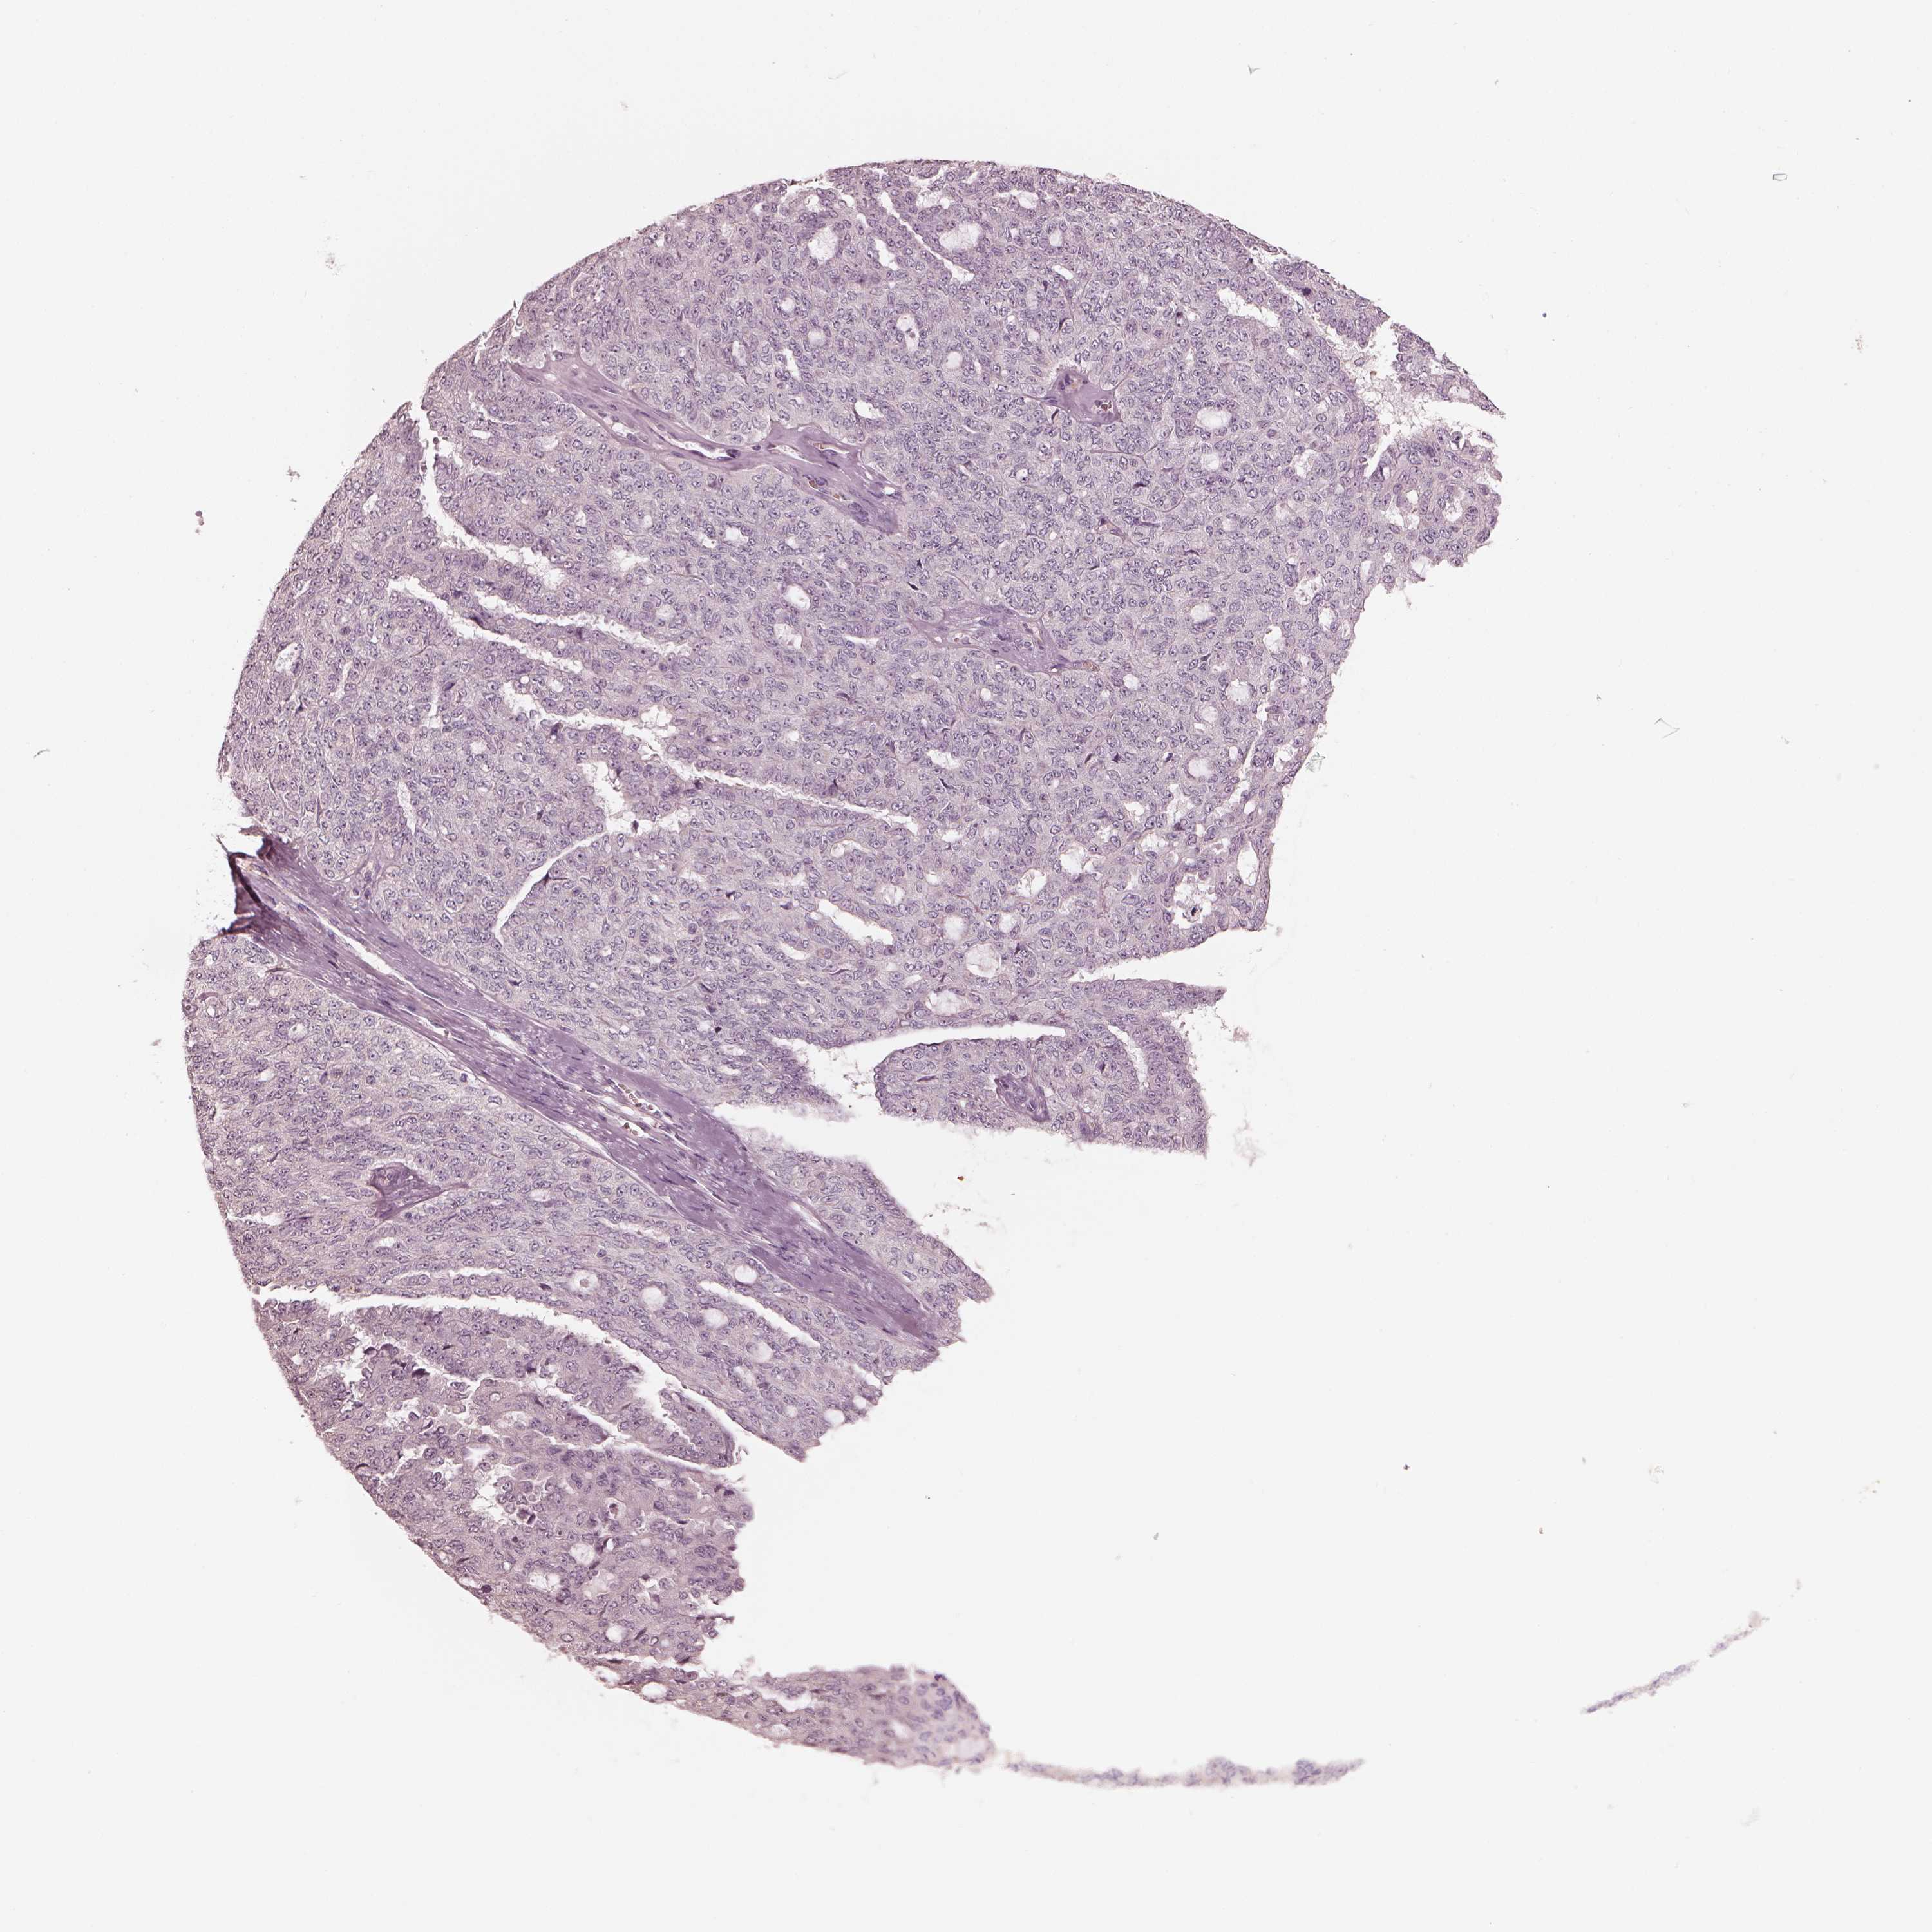

OVARIAN CANCER - Protein expressioni

A mouse-over function shows sample information and annotation data. Click on an image to view it in a full screen mode. Samples can be filtered based on level of antibody staining by selecting one or several of the following categories: high, medium, low and not detected. The assay and annotation is described here.

Note that samples used for immunohistochemistry by the Human Protein Atlas do not correspond to samples in the TCGA dataset.

Antibody stainingi

Antibody staining in the annotated cell types in the current human tissue is reported as not detected, low, medium, or high, based on conventional immunohistochemistry profiling in selected tissues. This score is based on the combination of the staining intensity and fraction of stained cells.

Each image is clickable and will lead to virtual microscopy that enables deeper exploration of all samples and also displays staining intensity scores, fraction scores and subcellular localization as well as patient and tissue information for each sample.

Antibody HPA073498

Cystadenocarcinoma, serous, NOS

Cystadenocarcinoma, mucinous, NOS

Carcinoma, endometroid